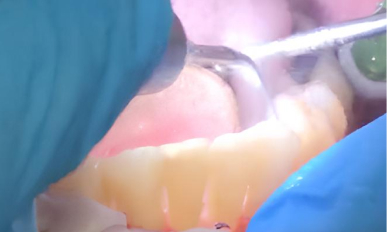

1. Подготовка: Пациенту провели профессиональную гигиену полости рта, удалив зубной камень и налёт. Затем выполнили местную анестезию (аппликационную) для обезболивания области лечения.

2. Лазерная обработка: Диодный лазер Medency Primo Triplo был настроен на длину волны 635 нм в режиме «периодонтит», с пародонтологической насадкой 400 мкм. Лазерный луч осторожно направляли на воспаленные ткани пародонтальных карманов для удаления бактериального налёта, стимуляции заживления и уменьшения глубины карманов.